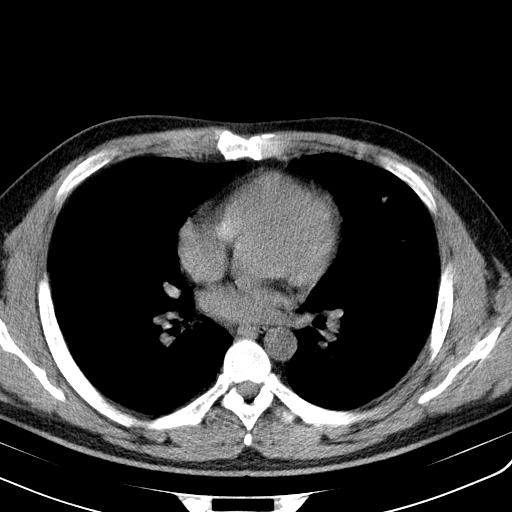

患者男性 35 主因发热咳嗽四天,血象不高,心肺听诊未见异常,无其它病史及传染病接触史。

两肺散在大小不等小结节影,下野较多,纵隔淋巴结增大。考虑:1、慢性血播性肺结核;2、霉菌病?3转移瘤待排。

两肺多发结节,部分病灶边缘不清,且示毛玻璃影。分布特点为沿血管支气管分布。

结合临床考虑;1,炎性肉芽肿性病变;霉菌?过敏性肺炎?2,韦格氏肉芽肿。3,转移瘤。